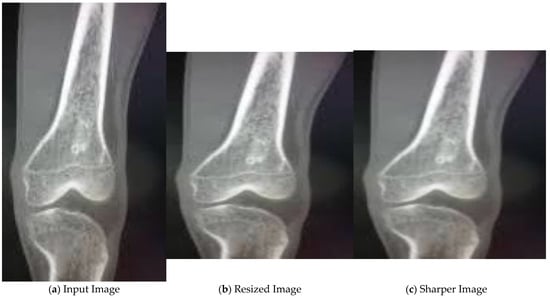

| Input: Bone X-ray image I Output: Classified image C 1. procedure FEATURE_EXTRACTION(dataset) 2. for I in dataset do 3. Read the image I←cv2.imread(image_path) 4. Resize the image 5. Apply median filter to remove noise from the image I←cv2.medianBlur(I, 3) 6. Extract the features from the filtered image using the VGG16 model feature_extractor←vgg16() f←feature_extractor(I) 7. end for 8. end procedure 9. procedure CLASSIFICATION(dataset, f) 10. Select the best features from the extracted features using mutual information statistic f s←SelectKBest(mutual_info_classif) 11. Split the dataset into training_dataset and testing_dataset 12. Train the SVM model with the features selected for the training_dataset classifier←SVC() C←classifier(fs) 13. Classify the testing_dataset using the selected features into healthy and malignant images 14. end procedure |

4.2. Results for Pre-Processing